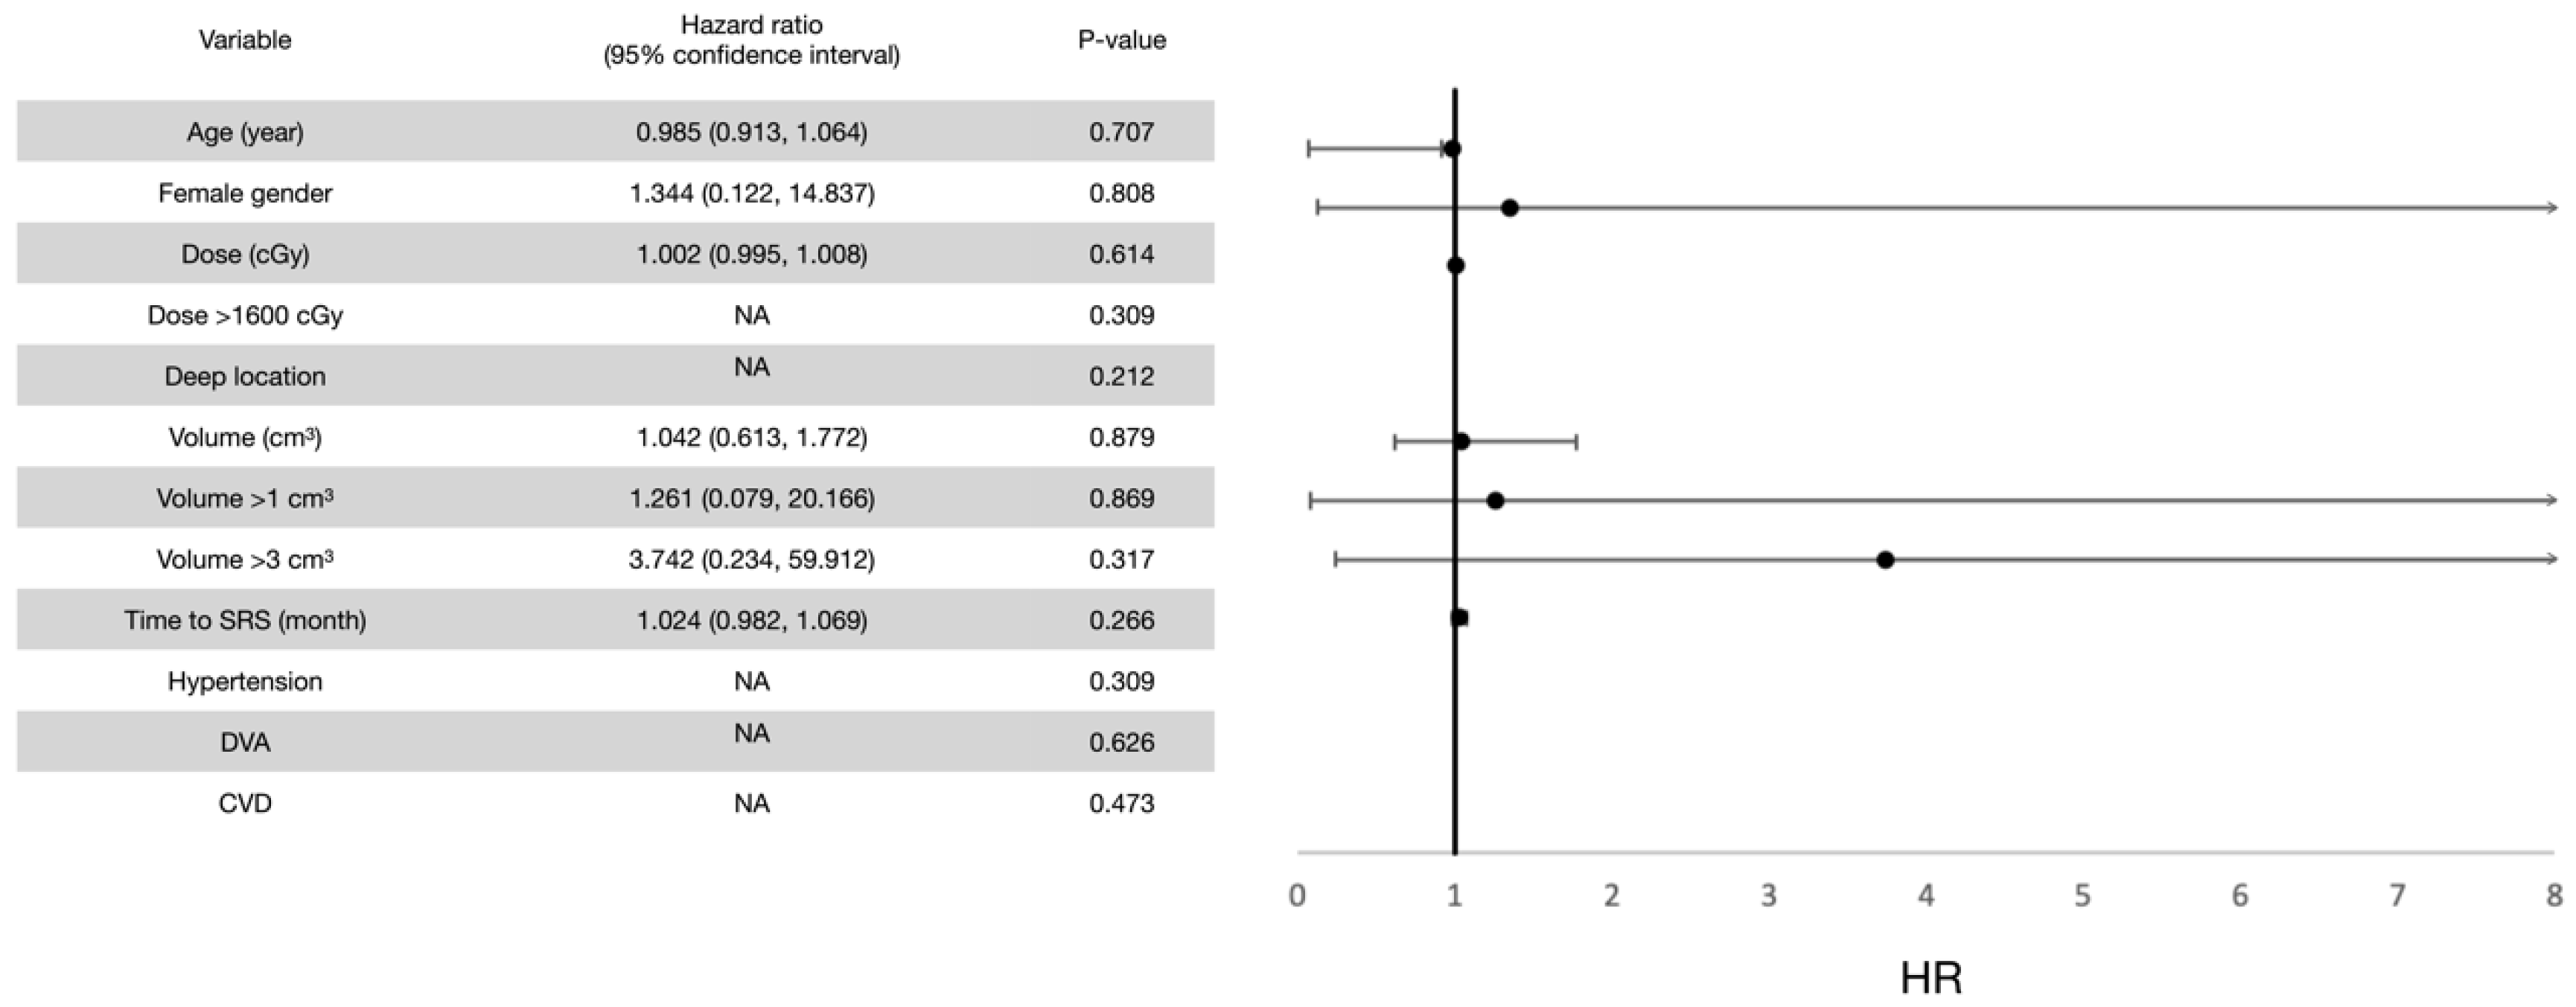

3.4. Post-Radiosurgical Perifocal Brain Edema

4.3. Post-Radiosurgical Adverse Radiation Effects